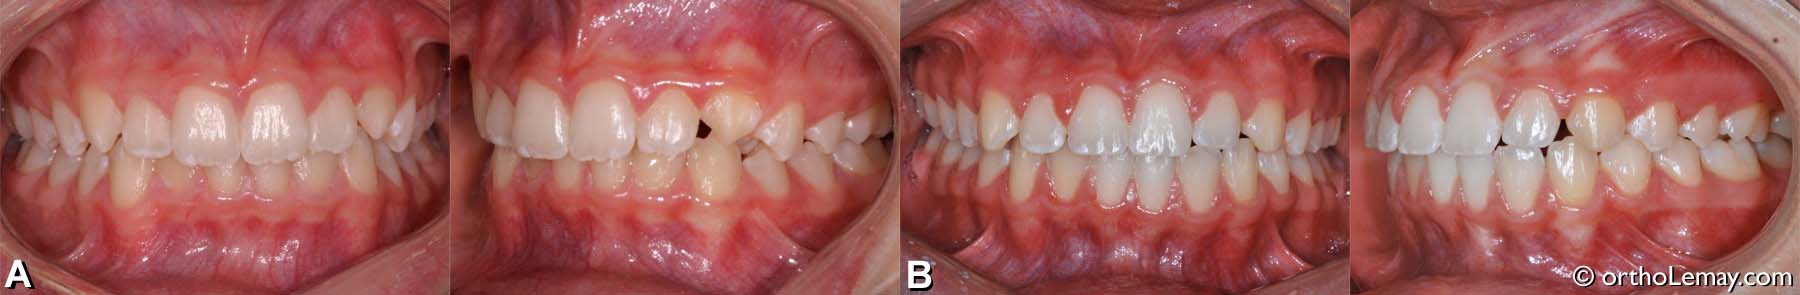

Exemple de traitement de malocclusion classe 1 (21)

(A) Légère malocclusion classe 1 , adolescente de 13 ans avec chevauchement dentaire.

(B) Correction du chevauchement, de l’overbite et des lignes médianes. L’espace entre l’incisive latérale supérieure gauche et la canine est dû à la forme de la latérale. Ceci pourrait être corrigé avec du matériau composite par le dentiste si cela était un problème esthétique pour la patiente.